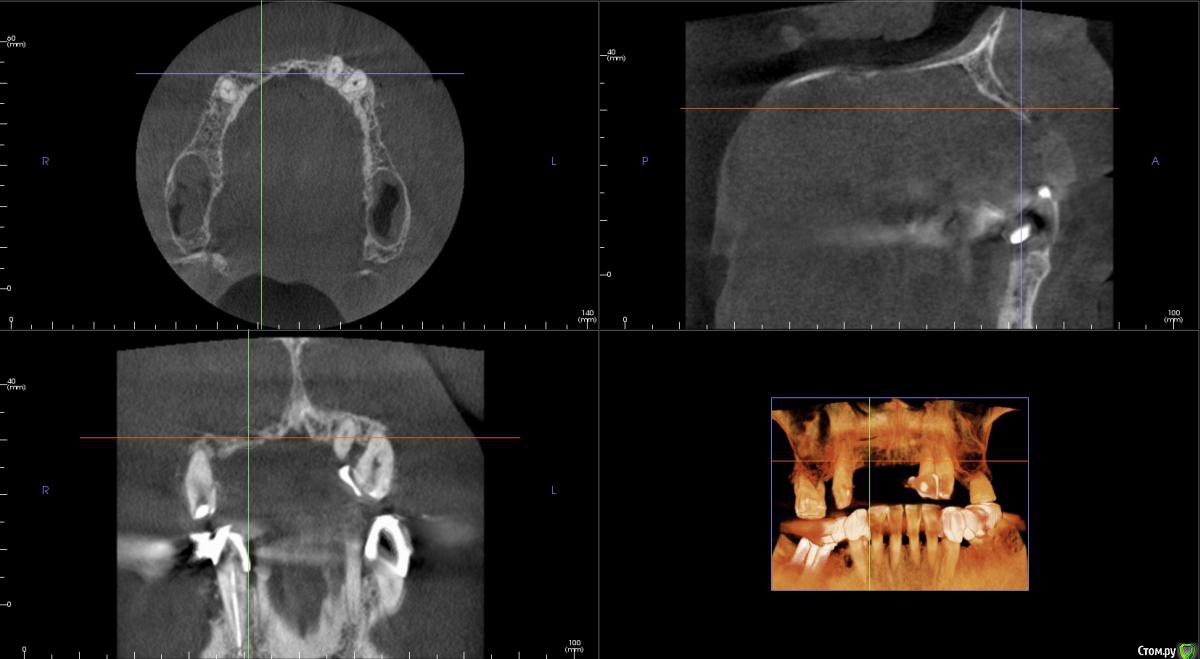

kamranchick Опубликовано 20 сентября, 2016 Поделиться Опубликовано 20 сентября, 2016 Интересует сторона 2. там хочу сделать соссидж, через несколько месяцев сделать закрытый синус и установить 2 винта в области 14 и 16, как вы думаете?и можно ли сделать конструкцию не брав во внимание фронтальный отдел? пациент финансово не тянет фронт Ссылка на комментарий

kamranchick Опубликовано 20 сентября, 2016 Автор Поделиться Опубликовано 20 сентября, 2016 Может убрать всё и на 4 ёх конструкцию предложить?думаю не получится, так как придется аугментировать и фронтальный отдел и боковой отдел чтобы по хорошему сделать все на 4, тем более я работаю на Осстем, а у нас мультиков в системе нет Ссылка на комментарий

колесников Опубликовано 20 сентября, 2016 Поделиться Опубликовано 20 сентября, 2016 думаю не получится, так как придется аугментировать и фронтальный отдел и боковой отдел чтобы по хорошему сделать все на 4, тем более я работаю на Осстем, а у нас мультиков в системе нетНе нужно там ничего аугментировать. Меняете корни на импланты. В обл премоляров так же есть объём по снимку. Иначе череда костных и мягкотканных пластик с неясным прогнозом. Пациент точно не потянет. У остема платформа 4.0 совместима с астровской 4.5-5.0. Можно у астры взять запчасти. Ссылка на комментарий